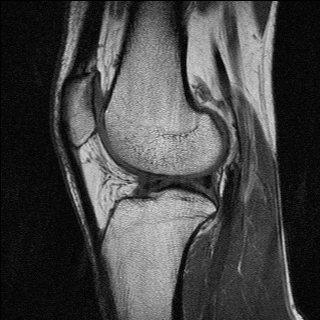

T1-weighted MRI images present a good contrast between fat, which appears dark, and water, which appears brighter. This type of contrast is used, for instance, in brain imaging to distinguish gray matter from white matter. Pathologies are often revealed by T2-weighted MRI. Edemas (abnormal accumulation of fluids) appear bright, while tumors often appear darker than normal tissues.

Examples of T1 and spin-density weighted images are shown in Figure 2.10.